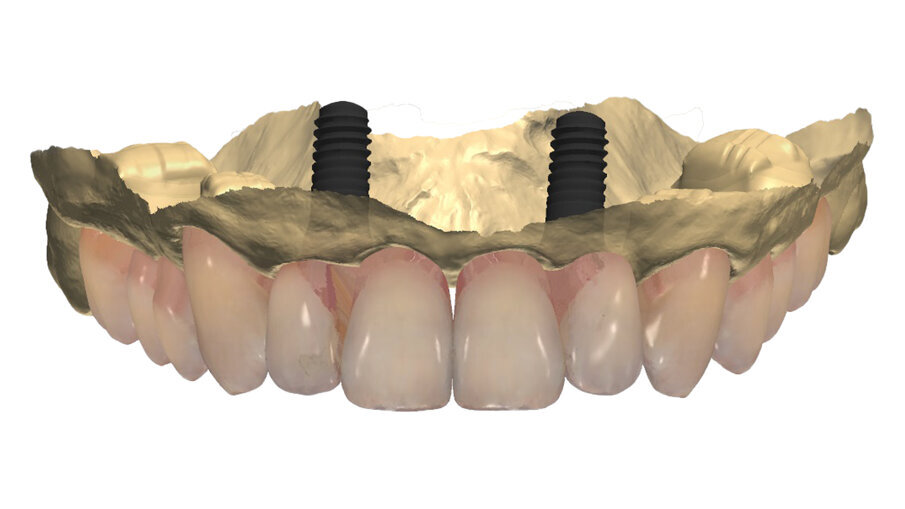

Per un’analisi completa in casi così compromessi è necessario il maggior numero di informazioni che dovranno essere raccolte partendo dal confronto con la paziente per quelle che sono le abitudini alimentari, la sua attività lavorativa, gli interessi sociali. Tutto ciò permette di capire quanto la paziente si aspetti dal nostro intervento ponendo la giusta attenzione all’estetica oltre che alla naturale funzione, è altresì importante rilevare delle immagini con e senza la protesi provvisoria in situ (Fig. 2). Nonostante si evinca la mancanza di congruità del manufatto protesico con la cresta residua la paziente ha mostrato difficoltà nel concepire una sua sostituzione per il timore di un peggioramento estetico. Il supporto di un progetto digitale ha consentito alla paziente di capire quale risultato potesse raggiungere a percorso ultimato. È evidente il collasso che il labbro superiore subisce quando viene rimossa la protesi con la rappresentazione del “codice a barra” dato dalla mancanza dei denti e della struttura ossea sottostante (Figg. 3, 4), a tal scopo è consigliabile poter fotografare la paziente nel profilo in entrambe le situazioni così da far emergere le discrepanze, anche nell’impronta digitale rilevata è importante acquisire il maggior numero di informazioni (Fig. 5). L’informazione diagnostica dettagliata è fornita dalla CBCT, pertanto abbiamo pianificato la sua esecuzione dopo la prima provvisorizzazione dell’arcata superiore evitando lo scattering da metalli presenti. Il file STL del wax-up (Fig. 6) associato al file STL dell’impronta senza provvisorio (Fig. 7) e al file DICOM radiologico (Figg. 8, 9) ha permesso una corretta progettazione chirurgico implantare (Fig. 10) nel rispetto della porzione ossea della cresta residua, ottimizzando la conseguente realizzazione della dima chirurgica (Fig. 11) per il posizionamento degli impianti in sede 1.2 e 2.2 (Figg. 12-14) anche nel rispetto della posizione degli elementi in antagonismo (Fig. 15).

Fig. 15_Nella visione di centrica è possibile valorizzare il progetto di posizionamento che ha tenuto conto della disponibilità ossea per sfruttare al massimo l’osso nativo, la posizione degli incisivi laterali, il parallelismo implantare il foro di fissaggio all’interno del cingolo coronale per non compromettere la porzione estetica vestibolare.